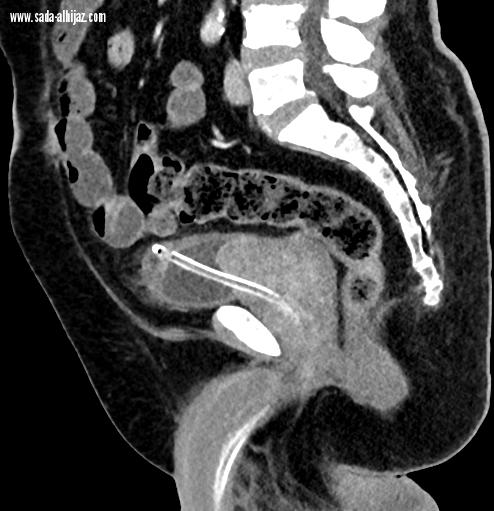

نجح بفضل الله فريق وحدة الأشعة التداخلية بمستشفى النور التخصصي بمكة المكرمة بالتعاون مع قسم جراحة المسالك البولية في إدخال خدمة جديدة و هي علاج تضخم البروستات الحميد المؤدي إلى إحتباس البول عن طريق الأشعة التداخلية.

وأبانت صحة مكة المكرمة بأنه تم تقديم هذه الخدمة لمريض سبعيني يعاني من إحتباس البول المزمن بسبب تضخم البروستات الحميد و عدم الاستجابة للأدوية و الإعتماد الكلي على قسطرة البول.

و نظراً لحالة المريض الصحية و التي تجعل من الجراحة التقليدية إجراء عالي الخطورة فقد تم تحويل المريض لأطباء وحدة الأشعة التداخلية و الذين قاموا بمعاينة المريض و مراجعة الفحوصات و عمل الأشعات اللازمة و من ثم اجراء العملية التداخلية بإستخدام التخدير الموضعي فقط .

وأضافت بأنه عند متابعة المريض على مدار الأشهر التالية فقد تحسن فيها إحتباس البول بشكل كبير و تمت إزالة قسطرة البول بشكل نهائي.

تجدر الإشارة أن هذا الإجراء الطبي يعتبر أحد الاجراءات الطبية الحديثة و المثبتة علميا بمنفعتها لمثل هؤلاء المرضى